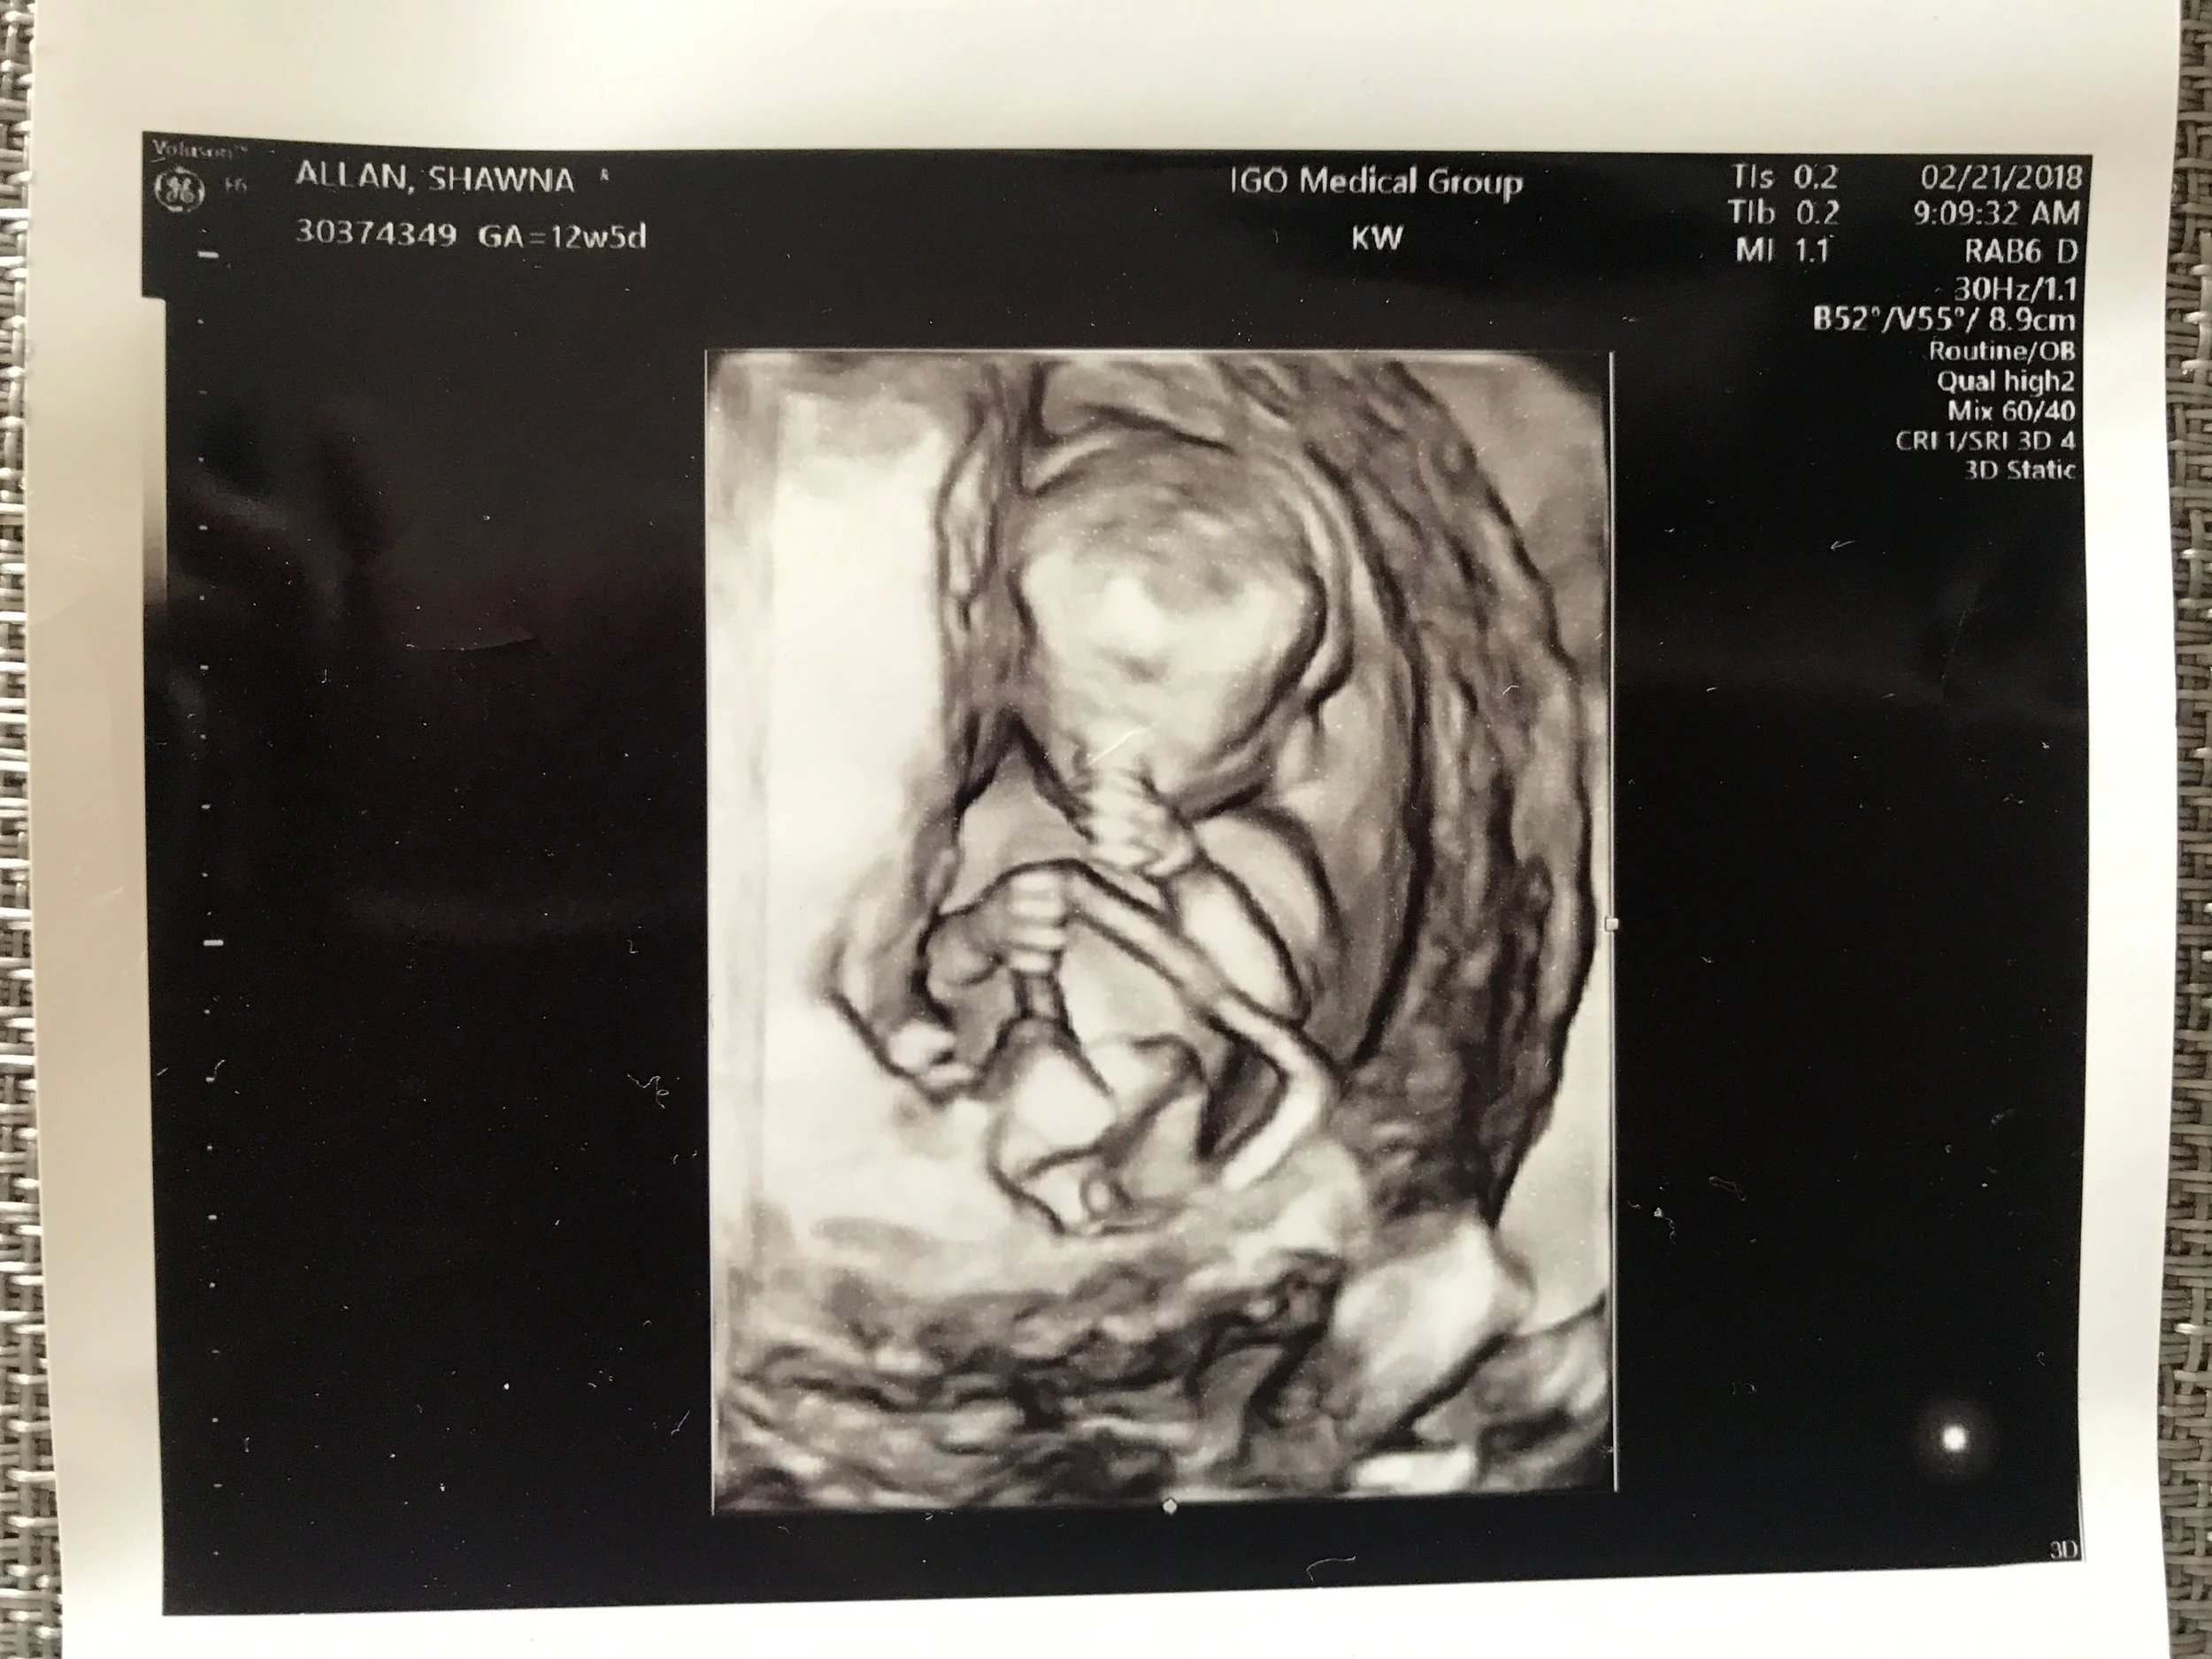

12 Week Ultrasound

Everything about this pregnancy has been nothing short of amazing. I got pregnant naturally. I didn't have to take one medication. I'm not on Lovenox injections. I have been able to stay active; I'm still running weekly and taking sculpt yoga classes. I can lift my son. Overall, I feel great (besides the morning sickness that finally went away around week 11) I am enjoying this experience and am so much more relaxed this time around. It's been such a blessing to be able to experience pregnancy the right way. If I didn't before... I absolutely believe in miracles now and the proof is growing in my belly.One of the reasons I wanted to start a blog was to share my struggles with infertility, but our process was still ongoing until recently. I’m sharing my journey now to give other women out there struggling to become a mom hope and to let them know that they’re not alone, even though you may feel like you are. I hate that we had to go through everything that we had to go through. But even I couldn't think of a better ending. Our story has a lot of hope and that's what's important.Despite the countless obstacles and challenges we have had to deal with, we got here and it was all worth it. Want to know what were having? Our Gender Reveal is here. Thank you for reading my entire story. The support and emails from other women going through infertility have touched my heart and made me feel so happy that I finally found the courage to share mine. Again, if anyone feels comfortable enough to share their fertility journey with me, I would be honored to hear from you ♥ You can email me at INFO@peacelovestyle.com